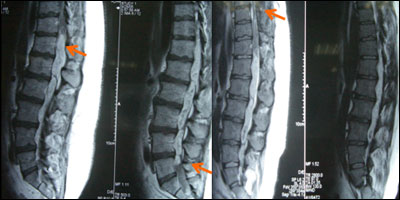

术后图片:

术后:感觉平面下降,腰痛缓解;随访发现臀部疼痛加重,伴便秘,双下肢肌力减弱,在他人扶持下行走。患者术后2月来院要求二次手术解除腰椎管内占位。术中见肿瘤位于硬膜下、部分来自圆锥髓内,紫红色,血运丰,向各椎间孔、隙浸润生长,全切肿瘤后,考虑脊柱的稳定性受影响,予以内固定治疗。术后病理回报为室管膜瘤,将第一次病理片子送到外院复审,认为其形态符合室管膜瘤,两处病变是同一性质的肿瘤。